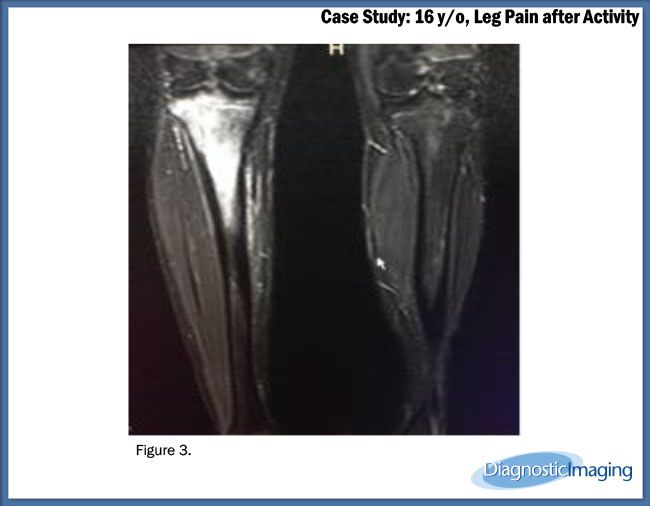

Case History: 16-year-old male developed right leg pain after playing basketball while wearing sandals.

Case History: A 16-year-old male developed right leg pain after playing basketball while wearing sandals.